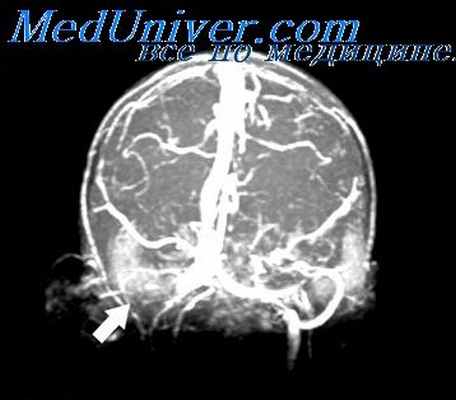

Наиболее частый путь распространения инфекции – внутричерепные венозные синусы (сигмовидный и каменистый). Эти крупные вены имеют непосредственный контакт с костными границами среднего и внутреннего уха, поэтому при наличии выраженного отита воспалительный процесс затрагивает и вены – так развивается флебит.

- Лучевые методы диагностики. По данным КТ височных костей может определяться деструкция сосцевидного отростка, исчезновение контуров пещеры среднего уха или наличие вместо нее узкого участка просветления с четкими границами, слияние антрума и аттика. При подозрении на синус-тромбоз выполняется синусография.